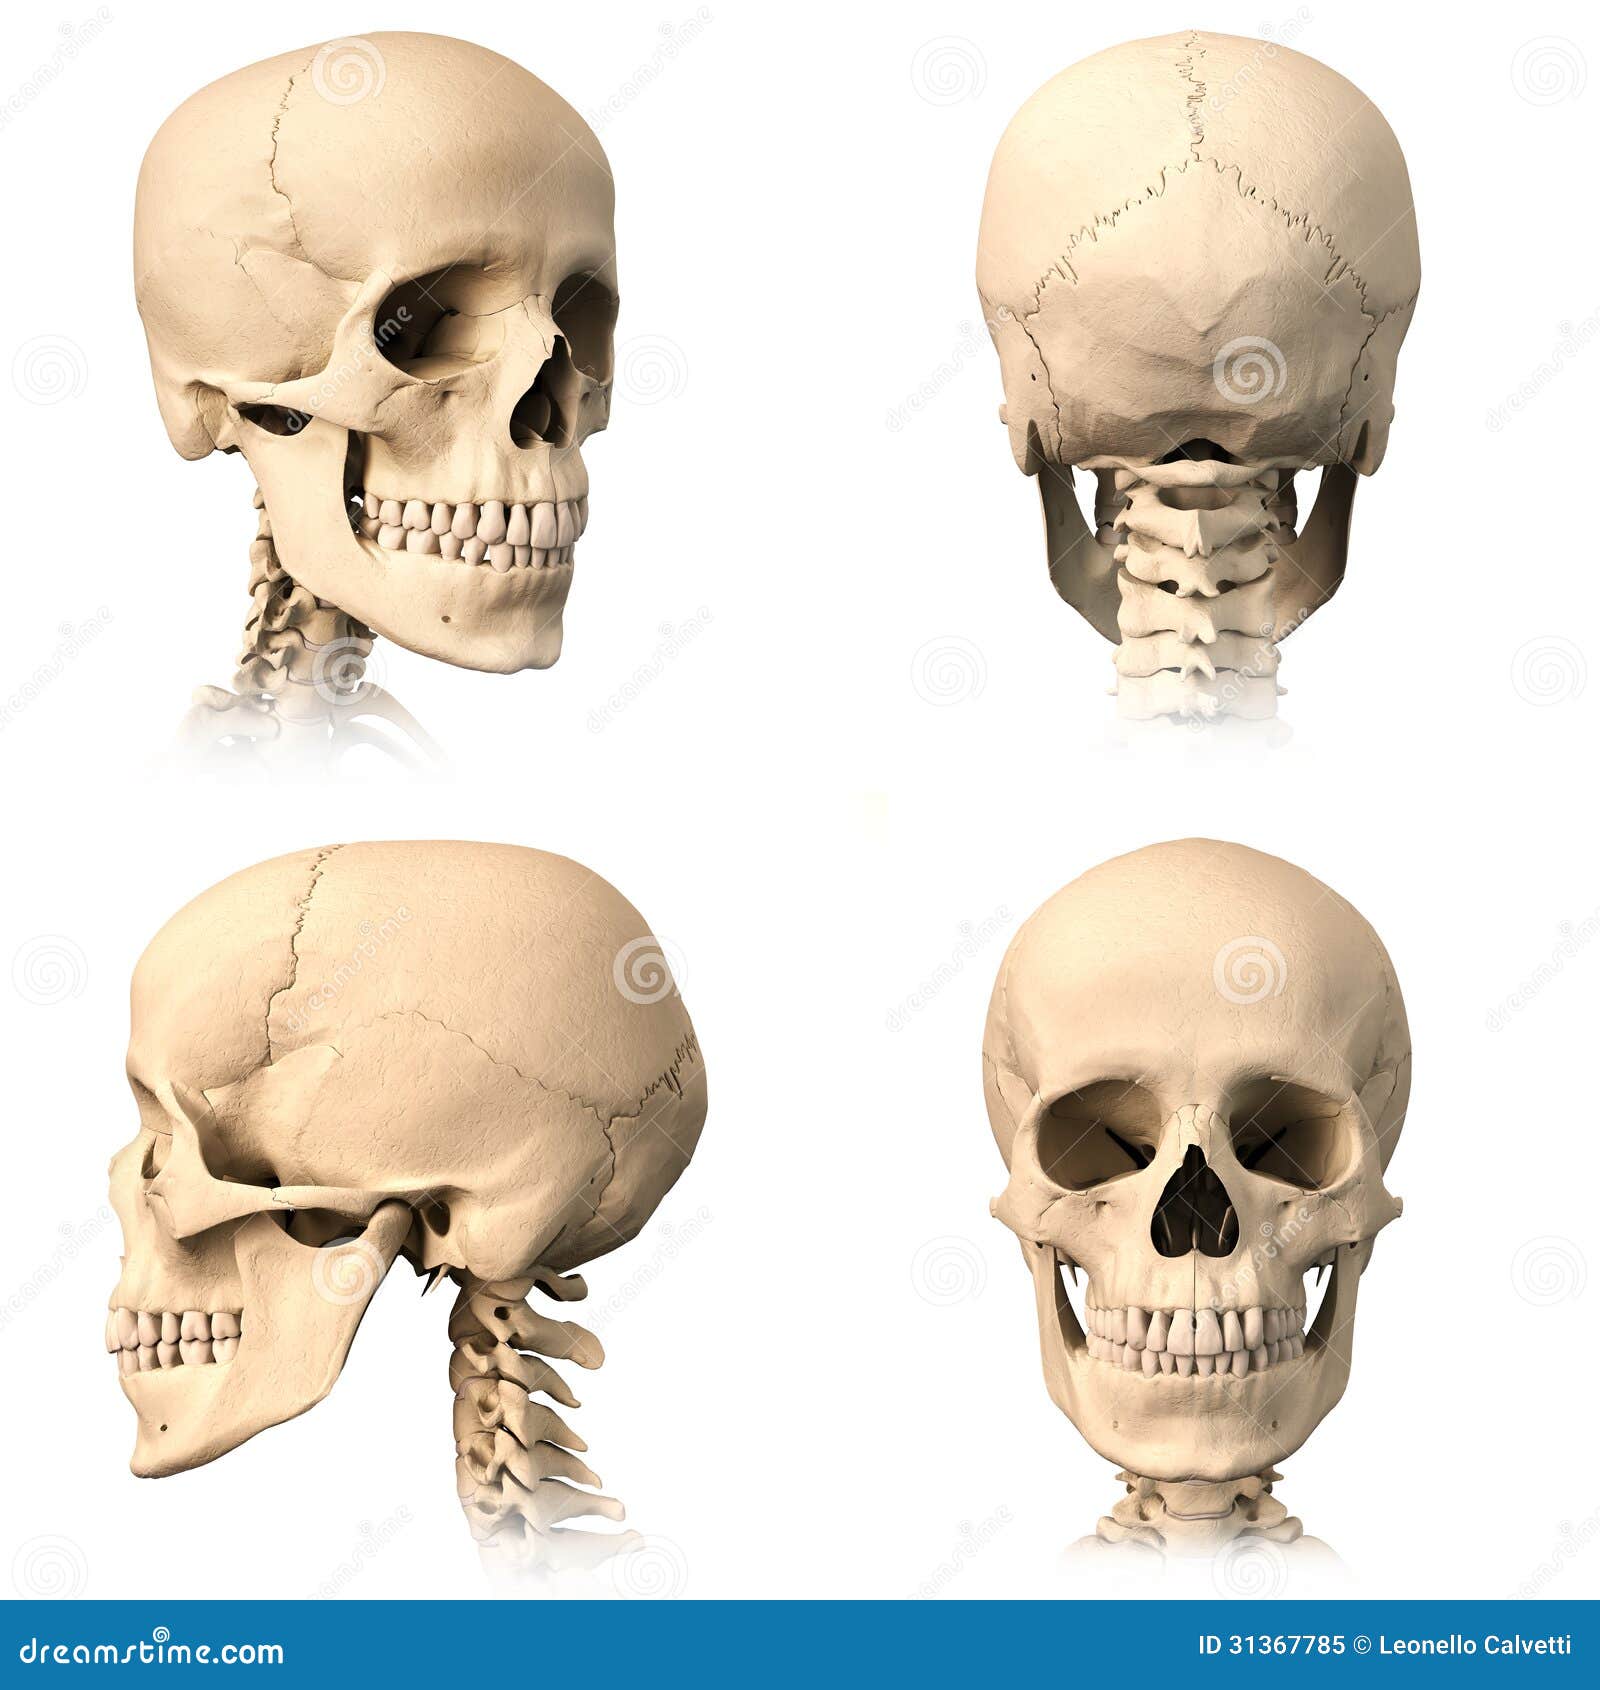

Prepare to be captivated by List, a showcase of real human skull front view black and white imagery powered by ieltschampions.edu.vn. More related visuals are below.

real human skull front view black and white

Posts: real human skull front view black and white